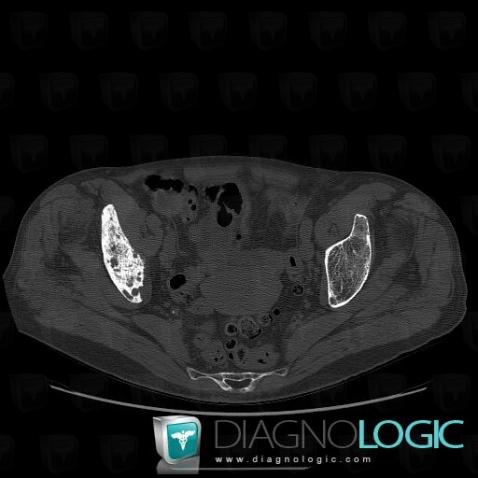

Metastasis, Ilium, CT

Here is the specific information in the key image above:

- Diagnosis Metastasis, Location(s) Ilium, with gamuts Generalised osteosclerosis